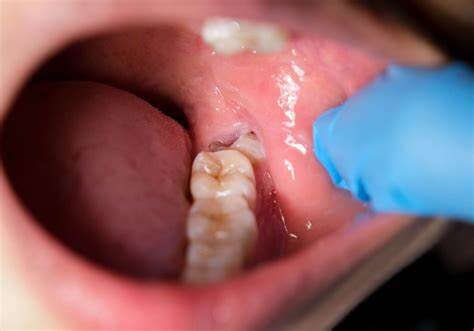

Cavities are pretty common. As the National Institutes of Health points out, the only condition more common than a cavity is the common cold. If you've never experienced tooth decay, you might wonder, "What does a cavity feel like?" The answer depends on the stage of the cavity and what foods you eat. Some foods, such as sweets, might trigger the pain of a cavity more than others.

How Cavities Form

Your mouth is naturally full of germs. Some of those germs are perfectly healthy, but others can be harmful. When you eat something sugary, such as candy or even potato chips, or drink a sugary beverage, the germs feed on the sugars in the substance. This produces acid, which is strong enough to wear away tooth enamel if not cleaned off quickly enough. In the end, a dental cavity begins to form.

In the early stages, a cavity can be reversed, as the National Institute of Dental and Craniofacial Research notes. Brushing your teeth with a toothpaste that contains fluoride can help restore the enamel and reverse the effects of cavities.

Signs of a Cavity

What does a cavity feel like? In the earliest stages, the answer might be nothing. There are no nerves in your tooth enamel, so when the decay is in that layer, you likely won't feel a thing. Once the decay has progressed enough to reach the softer tissues inside the tooth, where the dentin and nerves are, you might notice signs of a cavity. Your teeth might feel sensitive and you could feel some pain, especially after eating sweets, hot foods or cold foods. The pain can be fairly mild or sharp and intense. Some people with cavities also feel pain when biting down.

Depending on the size of the cavity, you may be able to see evidence of it in your mouth. Cavities sometimes create visible holes in the teeth. They can also create stains that are black, brown or white on the surface of the tooth.